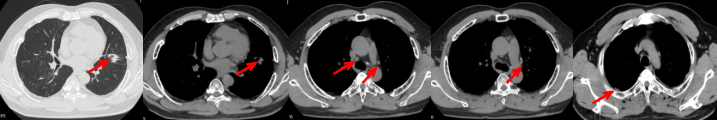

治疗经过:2024.08开始口服赛普替尼(160mg,bid)。2024.09复查胸CT评效PR。2025.1复查胸CT:右肺下叶外基底段见一不规则形实性肿块,大小约94mm×87mm,边缘呈分叶状,其内密度不匀。右侧胸腔见少许水样密度影。评效PD,PFS=5个月。患者未同意再次组织活检,目前应用卡博替尼治疗,仍在随访中。治疗期间未出现毒性反应。

2024.08

2024.09评效PR

2025.01评效PD